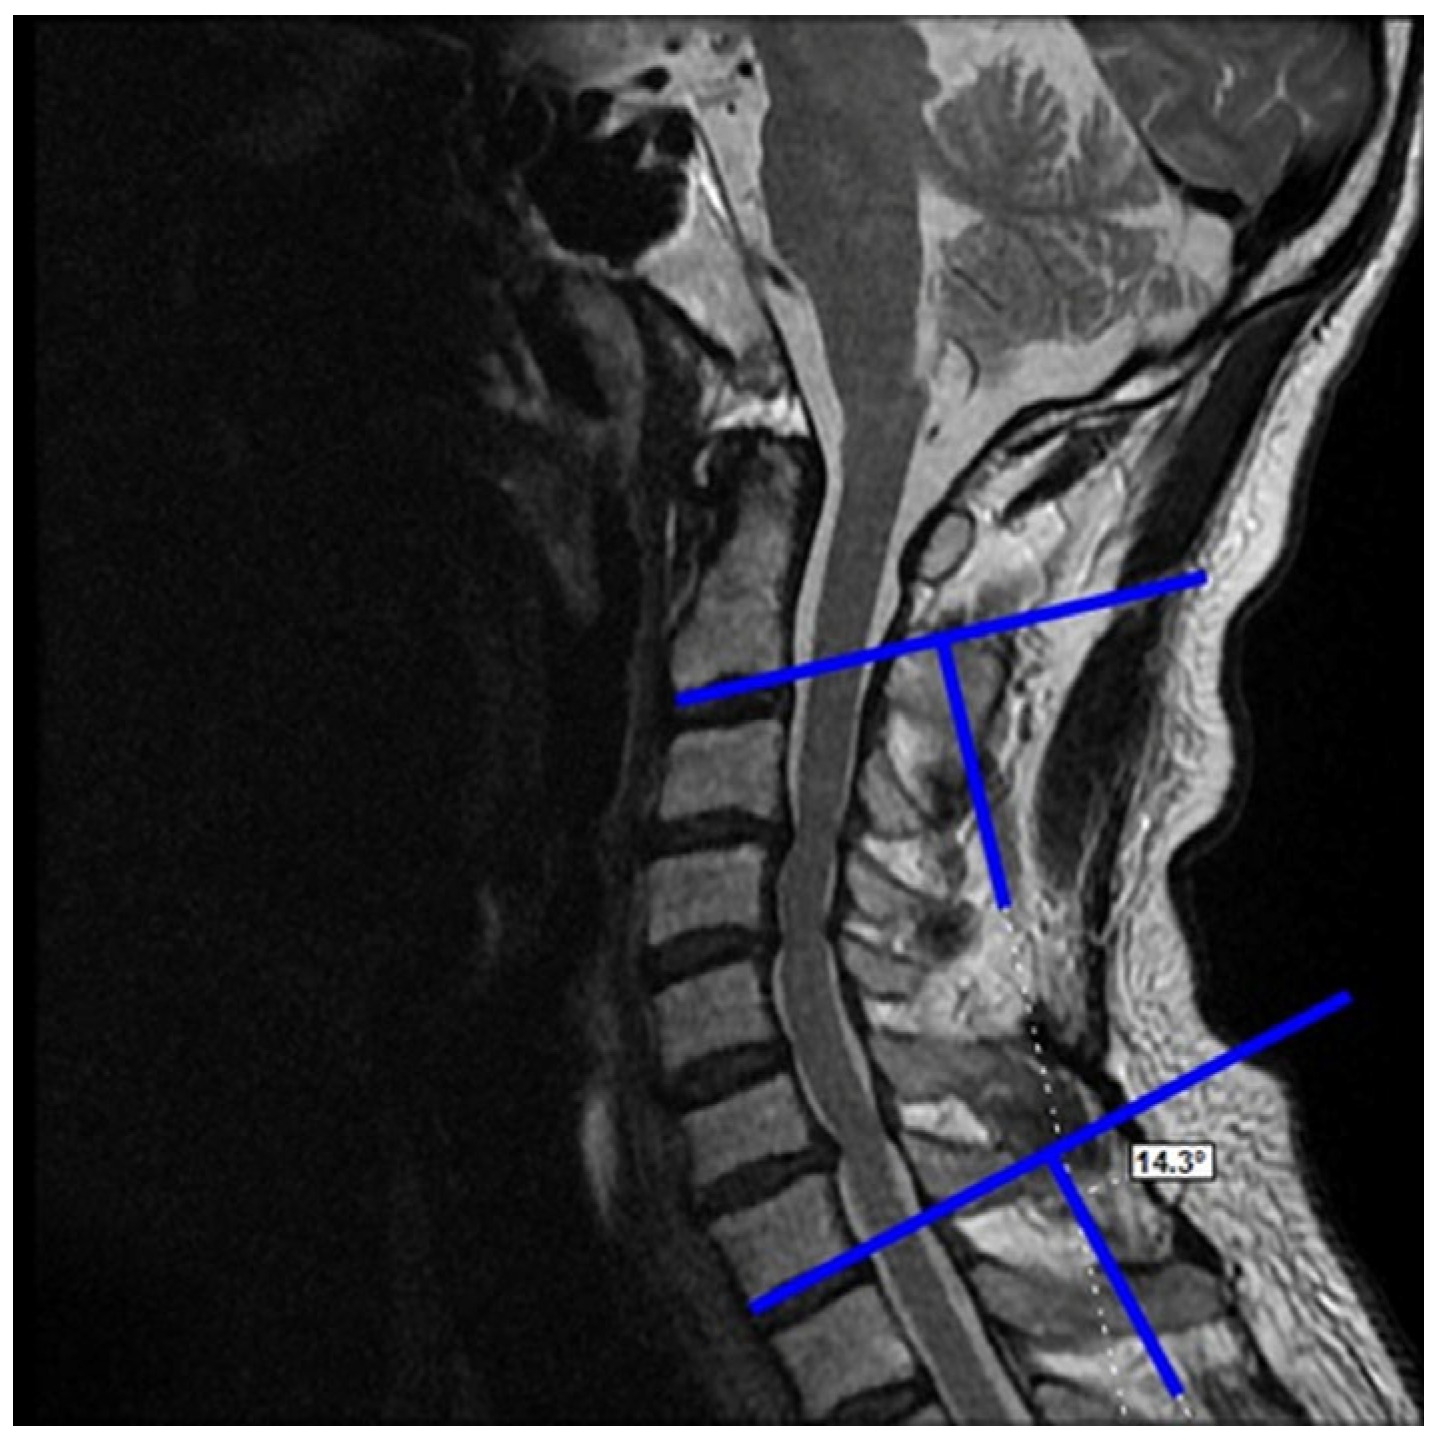

2.3. Dependent Variables (Radiological)

- Postoperative last control C2–C7 Cobb angle

Preoperative C2–C7 Cobb Angle vs. Postoperative Last Control C2–C7 Cobb Angle